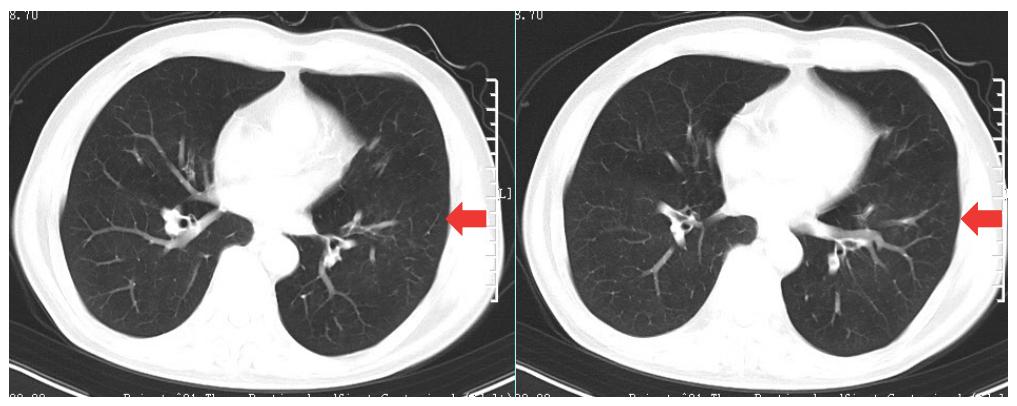

胸部CT:两肺上叶纤维条索灶及钙化灶。两肺上叶气肿伴肺大泡,左肺下叶结节,主动脉及冠脉硬化(图2)。

图2 入院时胸部CT

20220228 肺部低剂量CT平扫+冠状位重建:左肺下叶炎症,左肺下叶结节,建议抗炎后复查。两肺上叶纤维条索灶及钙化灶,考虑陈旧性结核可能。两肺上叶气肿伴肺大泡。胸膜局部增厚。主动脉及冠脉硬化(图5)。

图5 二次入院肺部CT

咳嗽症状显著改善。3月22日门诊复查左肺下叶炎症显著好转(图6)。

图6 复查肺CT